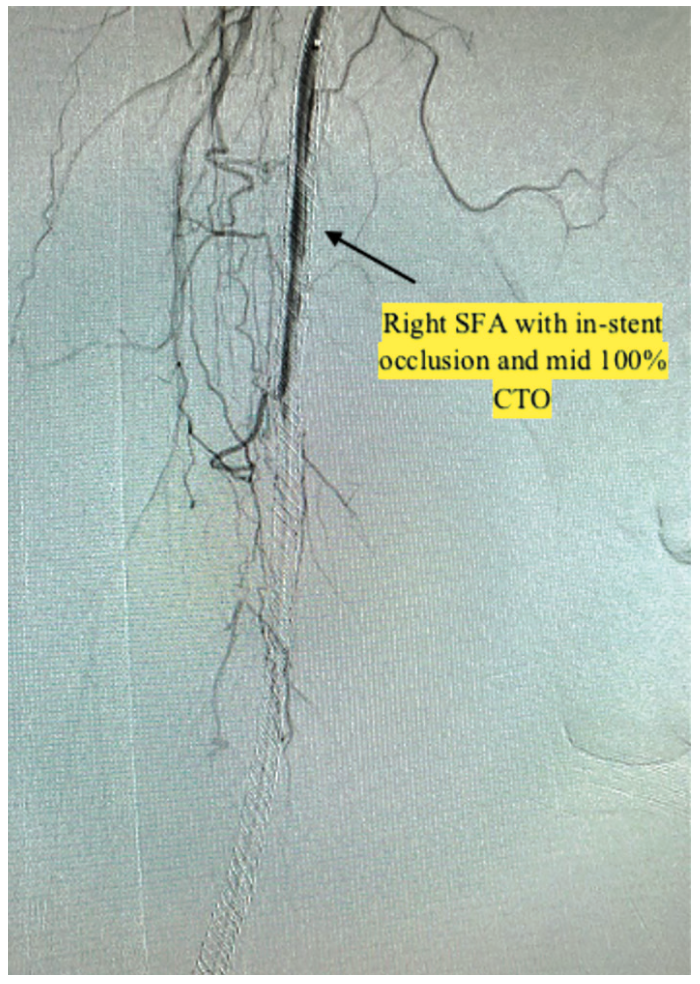

Transpedal right anterior tibial artery access was obtained using ultrasound guidance with a “dry stick”, and the initial angiogram through the sheath showed a chronic total occlusion (CTO) of the anterior tibial artery, with faint collateral flow to also-occluded peroneal and posterior tibial arteries (Figure 1). A subsequent selective angiogram was performed through a Rubicon support catheter (Boston Scientific), advanced from the transpedal sheath to the right external iliac artery. An angiogram with runoff to the foot showed the right SFA had a mid 100% CTO with in-stent restenosis. In addition, the anterior tibial artery was 100% chronically occluded, and the peroneal and posterior tibial arteries were 100% chronically occluded (Figure 2).

After reviewing the angiographic findings, the decision was made to intervene on the anterior tibial artery and SFA. Given the patient’s previous groin access complications along with his significant iliac tortuosity, we proceeded using only the single transpedal access obtained during the initial peripheral angiogram. An .009-inch Rotawire (Boston Scientific) was advanced into the right external iliac artery from the pedal sheath. We performed rotational atherectomy of the chronically occluded SFA and popliteal artery, followed by percutaneous transluminal angioplasty of the right anterior tibial artery and SFA CTO. At this point, we observed good flow in the right SFA and anterior tibial arteries, with a reduction of the stenosis from 100% to 0%. However, the tibioperoneal trunk was still occluded at the ostium (Figure 3). We attempted to advance several wires from the anterior tibial artery across the tibioperoneal trunk. We initially attempted to cross using our traditional peripheral wires, which include the Choice PT extra support (Boston Scientific) and Hi-Torque Command (Abbott Vascular) guidewires. Each attempt was unsuccessful, as the acute angle of the tibioperoneal trunk would cause the wires to prolapse into the popliteal artery. A 120-degree angled tip SuperCross support catheter (Teleflex) (Figures 4-5) was incorporated to help guide us across the acute angle of the occluded tibioperoneal trunk. However, the aforementioned peripheral wires would still prolapse into the popliteal artery and straighten the angled tip of the SuperCross catheter. We switched to a coronary Hi-Torque Whisper guidewire and using the 120-degree angled tip SuperCross support catheter to guide us across the acute angle of the tibioperoneal occlusion, the wire successfully advanced all the way down the peroneal artery (Figures 4-6). We advanced a 2.5 mm x 30 mm coronary Euphora balloon (Medtronic) over the wire and performed successive sequential balloon angioplasty of the proximal tibioperoneal trunk and the peroneal artery all the way to the ankle. An angiogram showed excellent flow post intervention, with 0% residual stenosis (Figure 6).